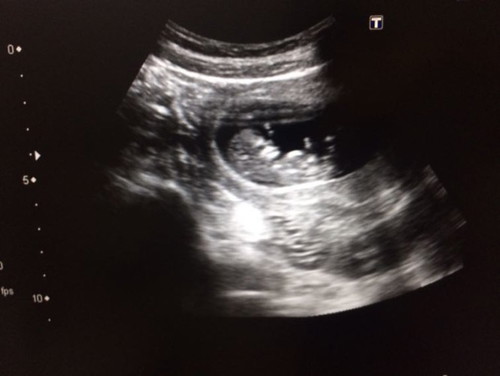

? 11 สัปดาห์แล้ว

บ้านนี้คุณหมอนัดซาวด์ 12w ตอนนี้ 11w ละจ้า ตื่นเต้นแทนคุณแม่เลยค่ะ ขอให้หนูน้อยแข็งแรงนะคะ